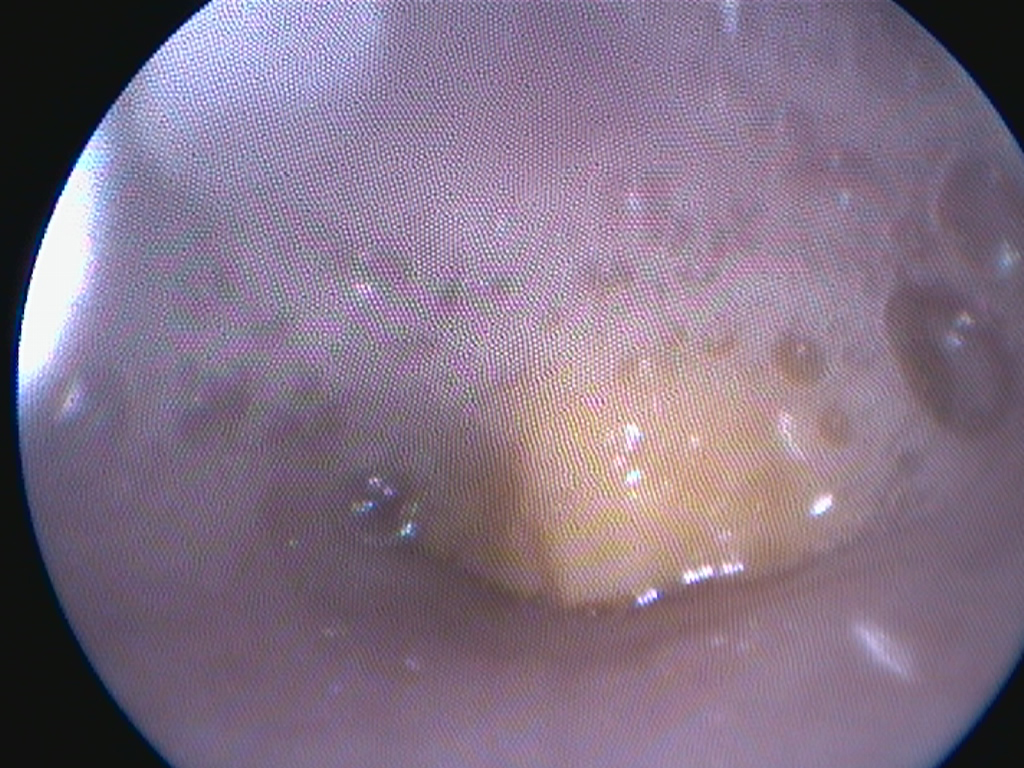

We hebben eerst in de slokdarm gekeken en kwamen inderdaad een stuk materiaal tegen wat klem zat.

Het lukte echter niet om het gemakkelijk eruit te trekken. De structuur zat zo klem, dat we met de tang steeds kleine stukjes eraf braken.